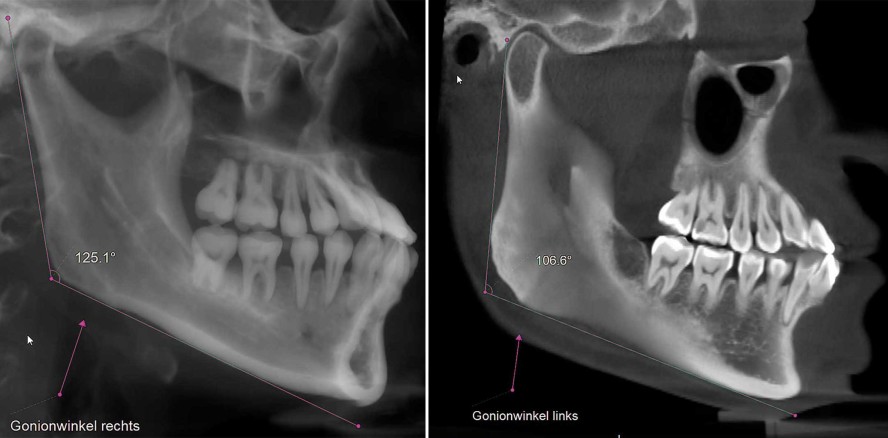

Bei unserer Patientin liegt zudem eine ausgeprägte Diskrepanz des Gonionwinkels vor. Während der Gonionwinkel auf der rechten Seite mit 125,1° sehr flach verläuft (Abb. 102), ist im linken aufsteigenden Ast ein steiler Gonionwinkel von nur 106,6° mit verkürzter Unterkieferlänge sichtbar (Abb. 103). Diese Verkürzung der anatomischen Struktur mag ebenso dazu beigetragen haben, dass die angewendeten Klasse III-Gummizüge auf der linken Seite und die Korrektur der Kondylusposition eine viel effektivere Wirkung gezeigt haben und es somit zu dieser verstärkten Distalverschiebung kam.